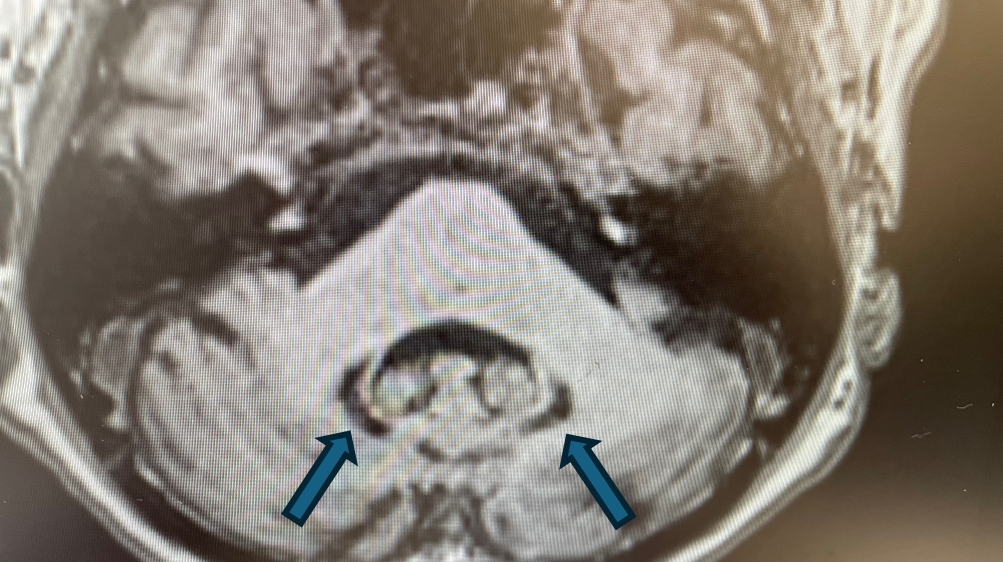

Rycina 2. Cechy akumulacji jonów żelaza w obrębie jąder podkorowych. (SWI).

rycina 2